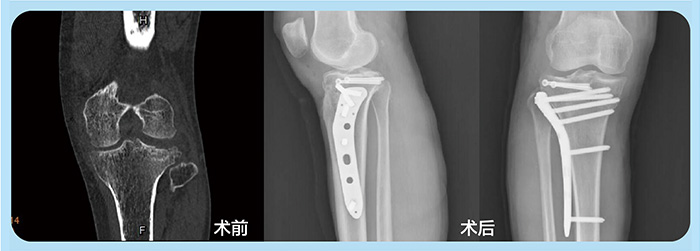

近日,53岁的何女士骑车时不慎摔倒,导致左膝关节受伤,被及时送到东北国际医院骨二科,原本送治非常及时,可病床上的何女士却愁容满面。

原来,送诊检查后何女士被确诊为左膝关节前交叉韧带止点断裂及外侧胫骨平台塌陷骨折,需要手术。听到“手术”两个字,爱美的何女士不仅担心手术会留下后遗症,更担心术后膝盖周围会留下显眼的疤痕。廖承杰主任了解后,认真评估病例并告知何女士较适用微创手术,它不同于以往大切口复位术,能通过微小的创口达到骨折复位及固定的目的,从而减少骨折部位附近的损伤,有效保留骨折周围血液供应,加快骨折早期愈合及功能的早期恢复。

8月27号,放下担忧的何女士顺利进入手术室。术中,在膝关节镜监视下,廖承杰主任通过对骨折处的透视定位,在皮肤小切口处建立胫骨隧道,将前交叉韧带胫骨止点撕脱骨折处以高强度缝线进行缝合复位固定,并将塌陷的平台复位,在平台下植骨支撑,几个巧妙的“小动作”顺利完成骨折复位,恢复平台关节面平整,并且仅仅用了几个1cm切口。术后不需石膏外固定,第二天她便可进行膝关节主动功能锻炼。目前,何女士恢复非常顺利,伤口愈合肉眼几乎看不出。

传统大切口复位后钢板固定术,手术切口大,软组织损伤大,剥离骨膜可能会影响骨折的愈合,术后患肢需要禁止负重,术中也无法像在关节镜下一样精确直视关节面及骨折复位。而微创骨折的内固定治疗手术是现代外科一种先进的手术技术,术中切口小,手术时间短,极大减少了组织暴露的范围和时间,有效降低了感染的发生;其次损伤轻,一般通过髓内或软组织间隙插入,减少骨膜破坏,骨折端的血供基本没有损伤,利于骨折愈合;重要的是可以进行早期关节及肌肉的功能锻炼,防止关节僵硬,肌肉萎缩等严重影响康复的并发症。